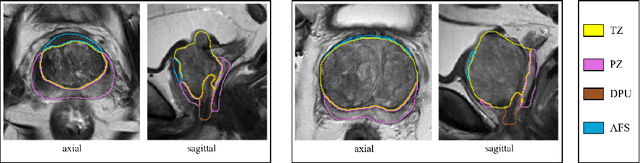

Abstract:Various convolutional neural network (CNN) based concepts have been introduced for the prostate's automatic segmentation and its coarse subdivision into transition zone (TZ) and peripheral zone (PZ). However, when targeting a fine-grained segmentation of TZ, PZ, distal prostatic urethra (DPU) and the anterior fibromuscular stroma (AFS), the task becomes more challenging and has not yet been solved at the level of human performance. One reason might be the insufficient amount of labeled data for supervised training. Therefore, we propose to apply a semi-supervised learning (SSL) technique named uncertainty-aware temporal self-learning (UATS) to overcome the expensive and time-consuming manual ground truth labeling. We combine the SSL techniques temporal ensembling and uncertainty-guided self-learning to benefit from unlabeled images, which are often readily available. Our method significantly outperforms the supervised baseline and obtained a Dice coefficient (DC) of up to 78.9% , 87.3%, 75.3%, 50.6% for TZ, PZ, DPU and AFS, respectively. The obtained results are in the range of human inter-rater performance for all structures. Moreover, we investigate the method's robustness against noise and demonstrate the generalization capability for varying ratios of labeled data and on other challenging tasks, namely the hippocampus and skin lesion segmentation. UATS achieved superiority segmentation quality compared to the supervised baseline, particularly for minimal amounts of labeled data.